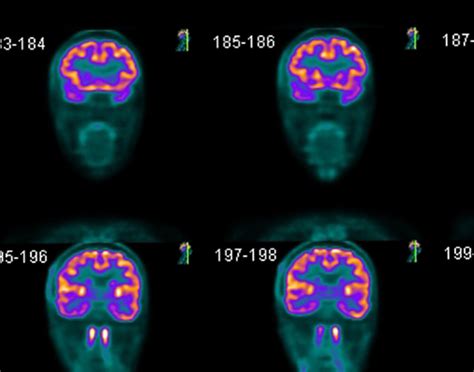

• Neurology: In neurology, PET scans are used to study brain function and diagnose conditions like Alzheimer's disease, Parkinson's disease, and epilepsy.

Interpreting Pet Scan Images requires specialized training and expertise. Radiologists and nuclear medicine physicians analyze the images to identify areas of abnormal metabolic activity. The interpretation process involves:

• Comparing the PET scan images with other imaging modalities, such as CT or MRI scans, to provide a comprehensive view of the body's structures and functions.

• Identifying areas of increased or decreased metabolic activity, which may indicate the presence of disease.

For example, in oncology, areas of high metabolic activity on a Pet Scan Image may indicate the presence of cancerous tumors. In neurology, abnormal patterns of tracer uptake can help diagnose conditions like Alzheimer's disease or epilepsy.